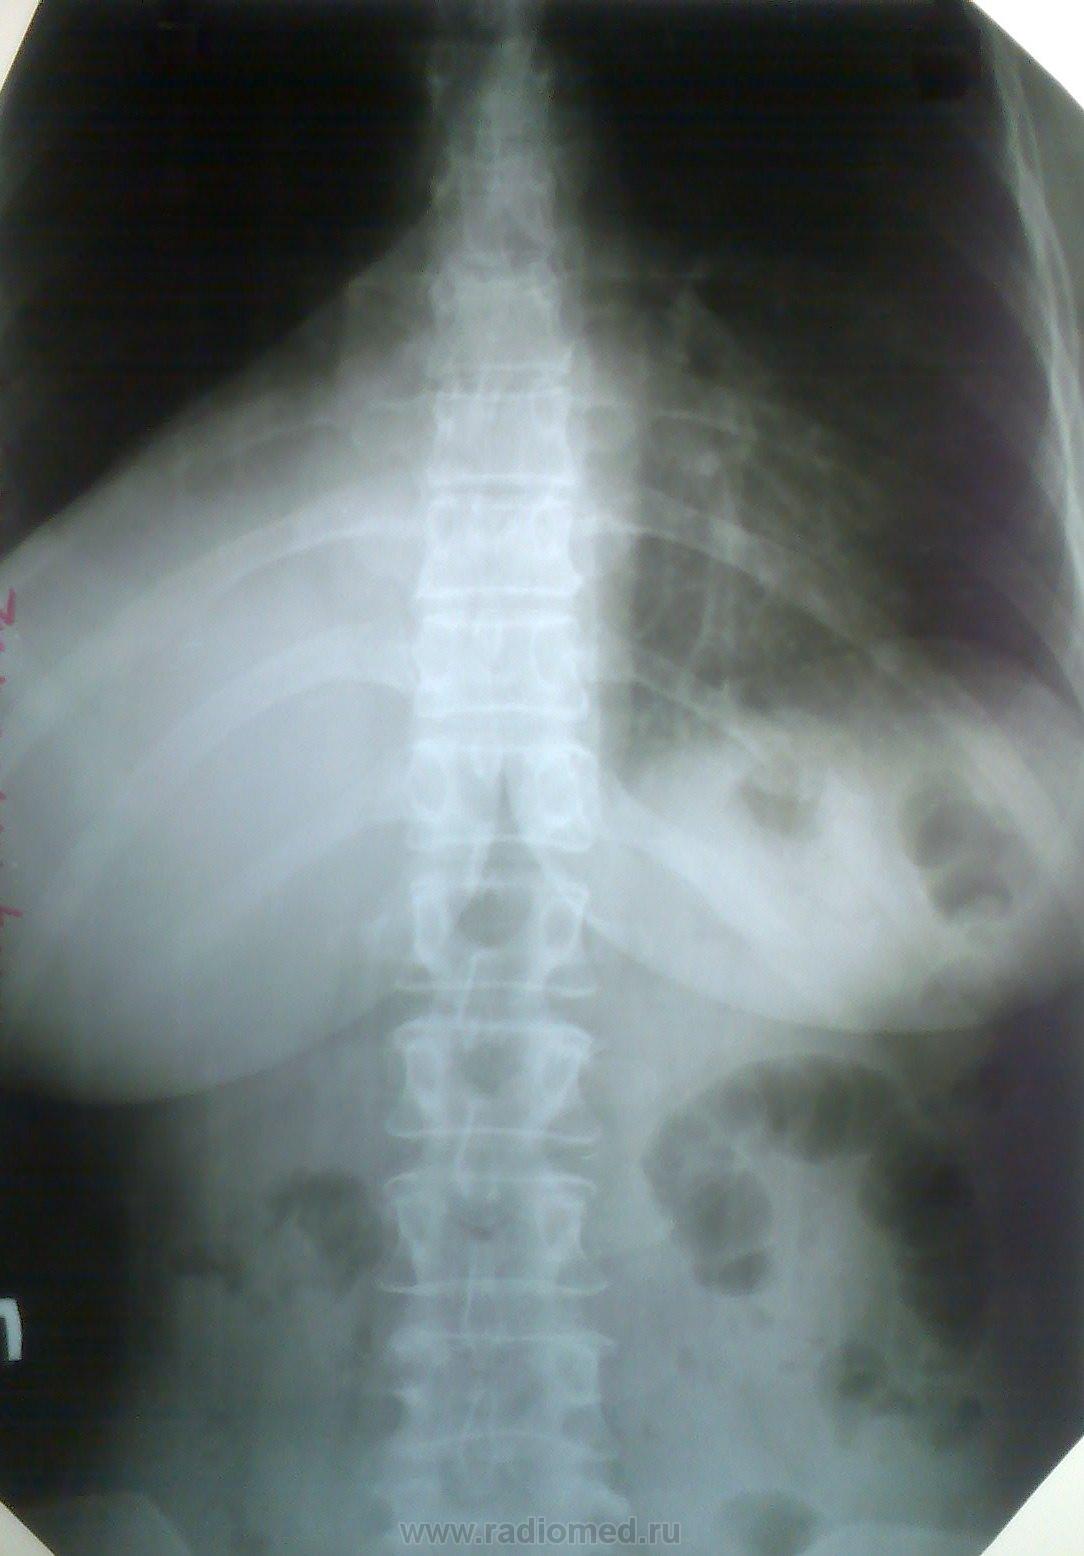

Дальше следует перерыв до июня...

06_2010_pryamoy.jpg06_2010_pr_bok.jpg

Потом были снимки в 7-м и 8-м месяцах

07_2010_pryamoy.jpg08_2010_pryamoy.jpg08_2010_pr_bok.jpg

И наконец, опуская снимки по ургентности, куоторые выставлял ранее, последние снимки - цифровые за 1.11.2010 Данные ирригоскопии не выставляю - полный ноль. Была, правда неудачная, попытка бронхоскопии, из анамнеза, лечилась в торакальном отделении, выписана с ПЛЕВРИТОМ, как утверждает сама. Вот такой случай. Что скажете теперь?

А что сказать? Обструкция н/д (промежуточного) бронха правого л-го, причем с июня-месяца. На реконструкциях культя. ФБС.

Я не могу понять как могли сказать все нормально.... Наверное сказали, потому что уже ничего нельзя было сделать... Ателектаз нижней доли.

Потом (на след снимках)  видно уже произошел ателектаз нижней доли справа :(

На КТ- все явно видно. + слева в области корня тоже какой-тоинфильрат (на 1 скане вижу, что эт оо такое - надо покрутить). + медиастинальная лимфаденопатия.

ФБС. И ОД, Скорее всего поняли что ничего уже не сделаешь...  Правада я по нескольким акиалам про это не скажу (надо видеть все исследование). Вообщим мой бфы диагноз (по представленным сканам) был бы центральный с-r правого легокго + ателетаз нидней доли + мтс в медиастинальыне лимфоузлы (прходже и контрлатеральные) + мтс в противоположное легкое. Кончено, возможнг, увидев все исследование, я бы изменил мнение...

Заключение практически слово в слово повторяет Ваше, только я добавил...ателектаз нижней и средней доли...

P.Sю Пересматриваю снимки- мда похоже аталектаз средней тоже. + гипервентиляция верхней (особенно на боковом впидно, как увеличено ретростернально епространвтсво и повышена его воздушность)

Да, гипервентиляция верхней доли справа очень показательна, как и симптом "кулис" по контуру атетектазированой части правого легкого.